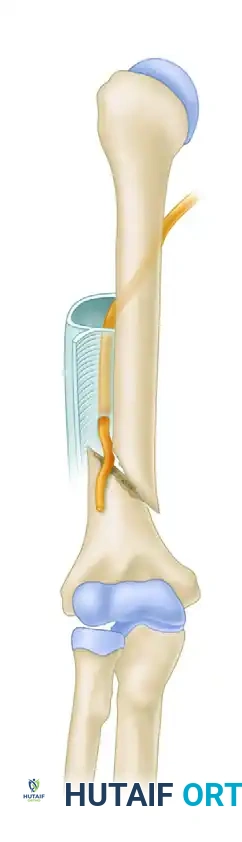

The radial nerve's vulnerability stems from its spiral course across the posterior aspect of the midshaft of the humerus (within the spiral groove) and its relatively fixed position in the distal arm. Approximately 10 cm proximal to the lateral epicondyle, the nerve pierces the lateral intermuscular septum to transition from the posterior to the anterior compartment. This tethering point renders the nerve highly susceptible to traction, contusion, or entrapment, particularly in specific fracture patterns.

The classic "Holstein-Lewis" fracture—a spiral fracture of the distal third of the humeral shaft—carries a notoriously high risk of radial nerve entrapment.

As illustrated above, the nerve is least mobile as it passes through the lateral intermuscular septum in the distal third of the arm.

In these oblique or spiral fractures, the distal fragment is typically displaced proximally and angulated laterally. Because the radial nerve is fixed to the proximal fragment by the lateral intermuscular septum, it can easily become trapped between the sharp cortical edges of the bone fragments, especially when closed reduction is attempted.